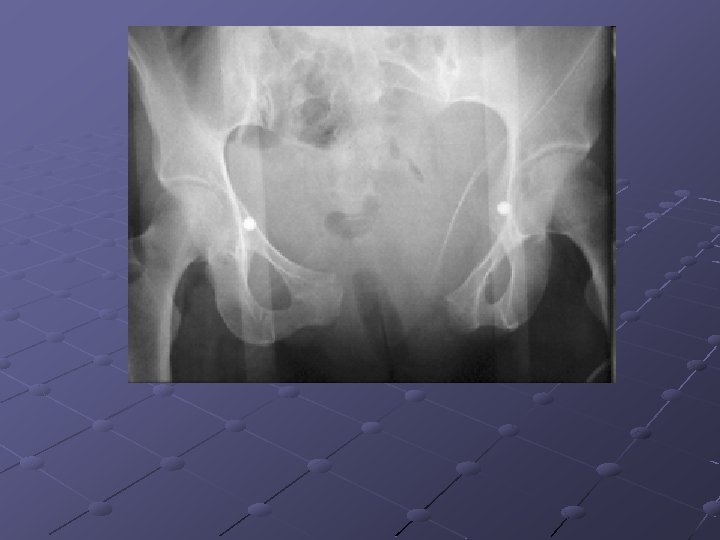

Imaging Studies

Pubic ramus fractures occur as parasymphysial fractures, midramus fractures, and pubic root fractures in association with distraction and compression injuries of the pelvis (Routt, Orthop Clin North Am, 1997). Displacement of pubic rami fractures may cause impingement or laceration of the bladder, vagina, and perineum, and, for these reasons, operative management may be considered. Operative treatment of pubic rami fractures is indicated to provide additional pelvic ring stability in association with posterior pelvic ring fixation. Stabilization of pubic rami fractures also may be considered in fractures involving the obturator neurovascular canal with accompanying neurologic injury. Treatment options for pubic rami fractures include external fixation, percutaneous screw fixation, and open reduction and internal fixation. External fixation with either multiple pins (Kellam, 1989) or single pins in each hemipelvis (Tucker, 2001) may be used successfully in conjunction with stabilization of posterior ring injuries to impart additional stability to the pelvic fixation construct. External fixation for pubic ramus fractures is indicated to impart additional stability after posterior pelvic ring repair and also when percutaneous or open treatment is contraindicated. Intramedullary fixation of pubic ramus fractures has been described for treatment of pubic rami fractures (Simonian, J Orthop Trauma 1994; 8(6): 476 -82; Tile, 1995). Intramedullary pubic ramus fixation with a 4. 5 -mm cortical screw has demonstrated fixation strength equivalent to plate fixation and has demonstrated good results in clinical settings (Routt, 2000; Simonian, J Orthop Trauma 1994; 8(6): 483 -9). Intramedullary stabilization of ramus fractures may be performed with either a percutaneous or open technique with either antegrade or retrograde screw placement in the pubic ramus. Extramedullary plate fixation is another option to stabilize pubic rami fractures after open reduction and usually is achieved with 3. 5 -mm pelvic reconstruction plates.